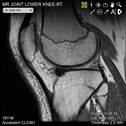

Stanford Musculoskeletal MRI atlas

MSK anatomy atlas, educational talks, and cases. ~1.7M pageviews.